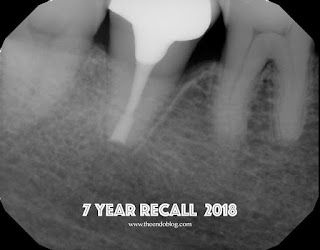

A seven year recall finds tooth #31 asymptomatic and fully functional.  While the mesial bone looks irregular, there is no periodontal pocket.  If you look at the initial photo of the extracted tooth, you can see the periodontal ligament, but there appears to be an area where the ligament had been lost.  There was not visible fracture on that area of the root at that time.  My assumption is that the pdl may not have ever reformed in that area - causing the current radiographic appearance. It is interesting how a perfectly good root canal and retreatment failed to give the desired results, but a last ditch effort with replantation has been successful up to this point.